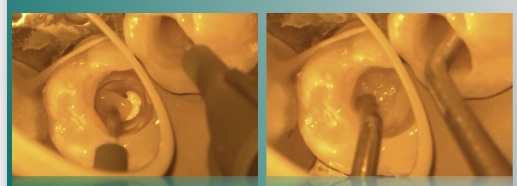

3%次氯酸钠大量冲洗,清理冠髓,暴露根管口,可见根管呈连续C形。

根充后髓腔内状态